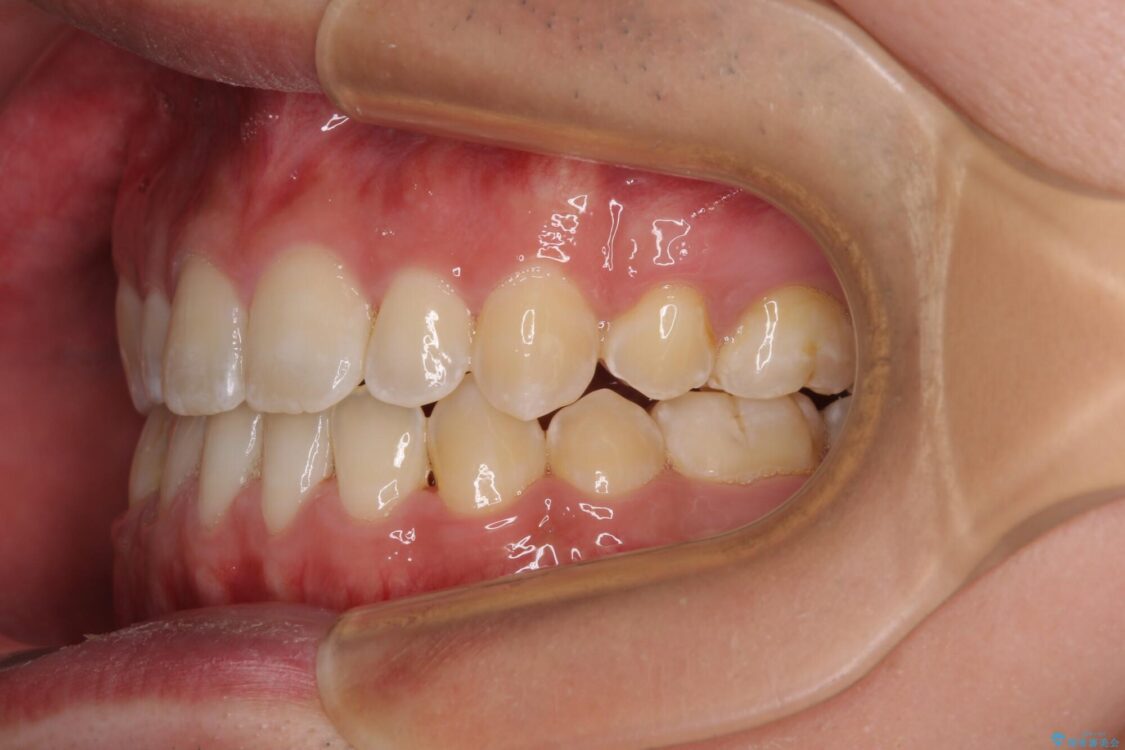

受け口傾向の咬み合わせと口元の突出感を気にして来院された患者様です。

治療前

• 口元の突出感を改善 受け口傾向の咬み合わせの抜歯矯正 治療前画像